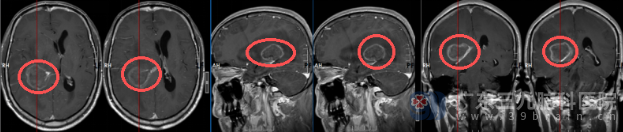

术前头颅MR检查提示: 1.右侧颞顶叶-侧脑室后角旁占位性病变,考虑转移瘤(其内少许渗血可能),伴右侧海马钩回疝、右侧大脑镰下疝,左侧侧脑室扩大伴间质性水肿; 2.脑膜转移待排; 3.脑白质高信号,Fazekas 1 级;